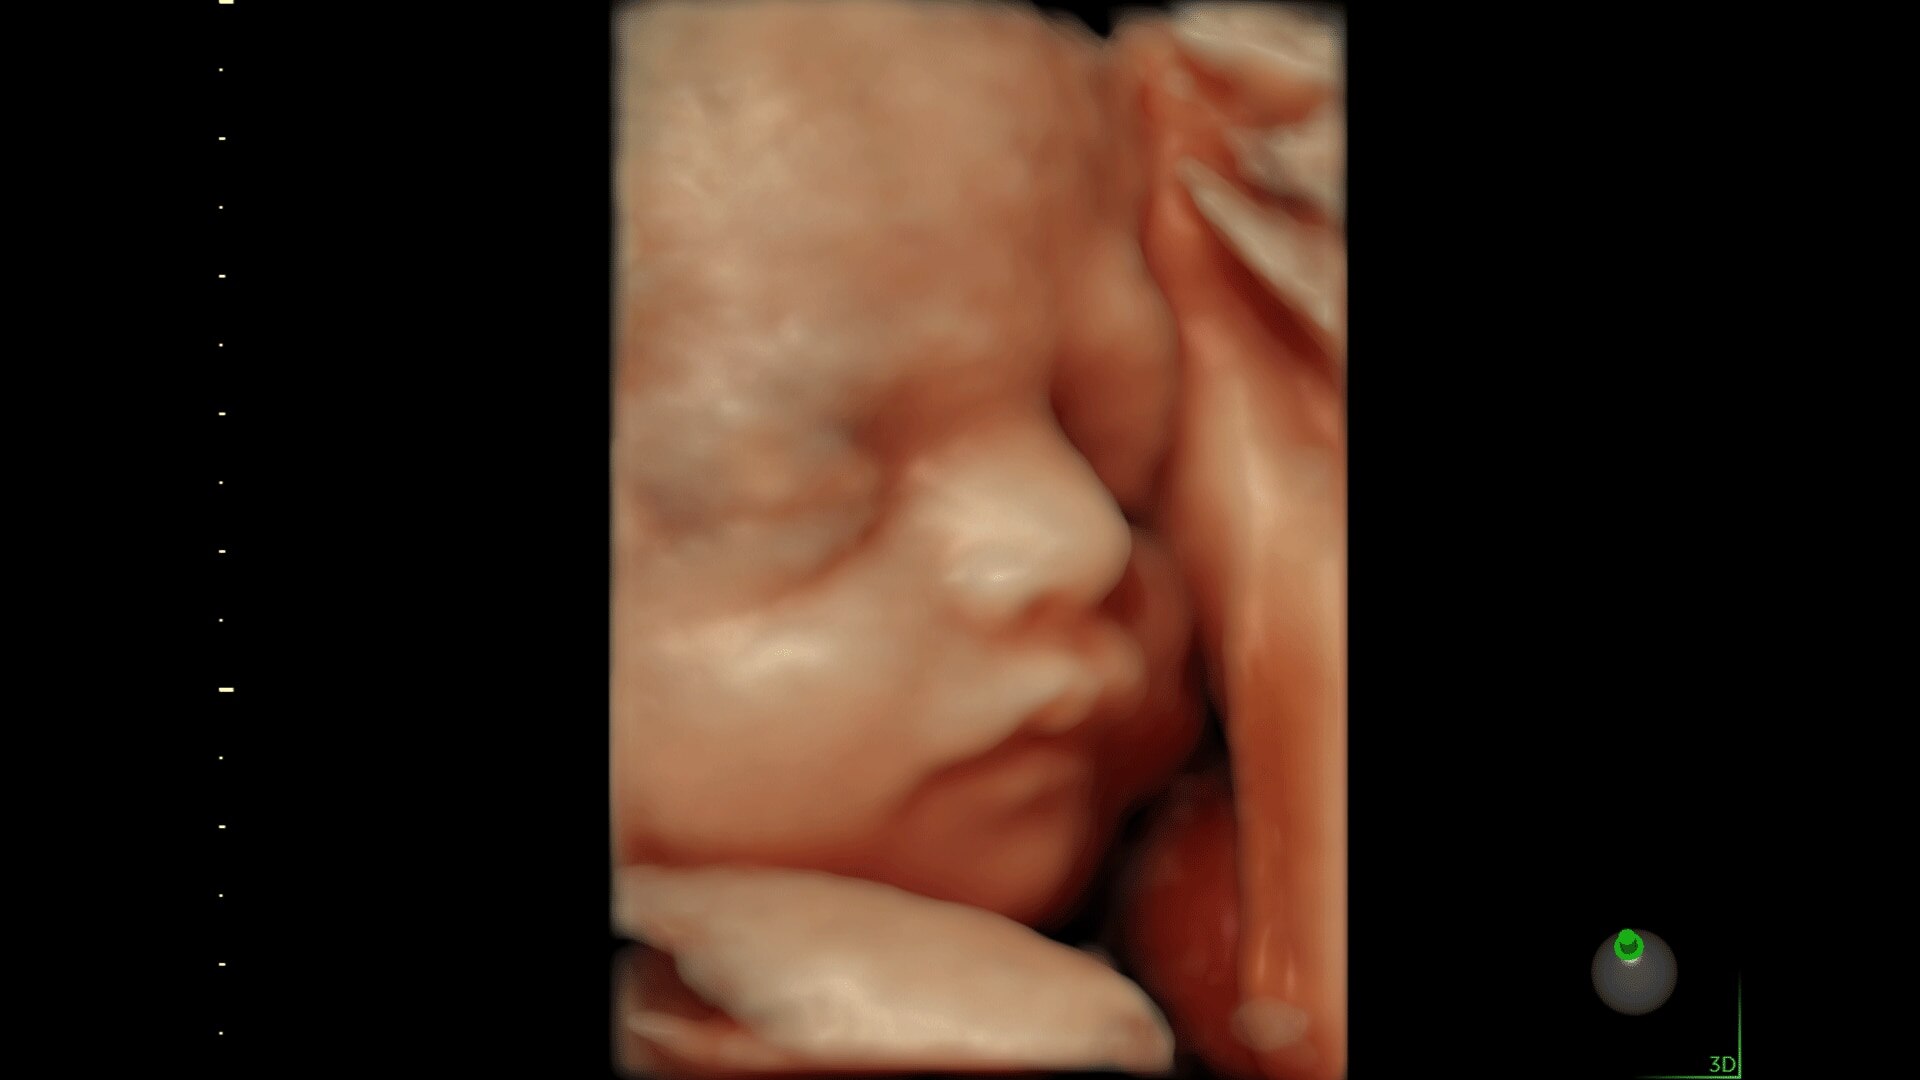

Generate spectacular 2D/3D and color Doppler images with increased penetration and stunning clarity, to help visualize critical details needed for diagnostic assurance. The Lyric Architecture unlocks new imaging and processing power to expand your imaging capabilities for years to come